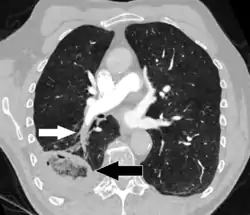

CT pulmonary angiography showing a "saddle embolus" at the bifurcation of the main pulmonary artery and thrombus burden in the lobar arteries on both sides.

Pulmonary embolism (white arrow) that have been long-standing and has caused a lung infarction (black arrow) seen as a reverse halo sign.